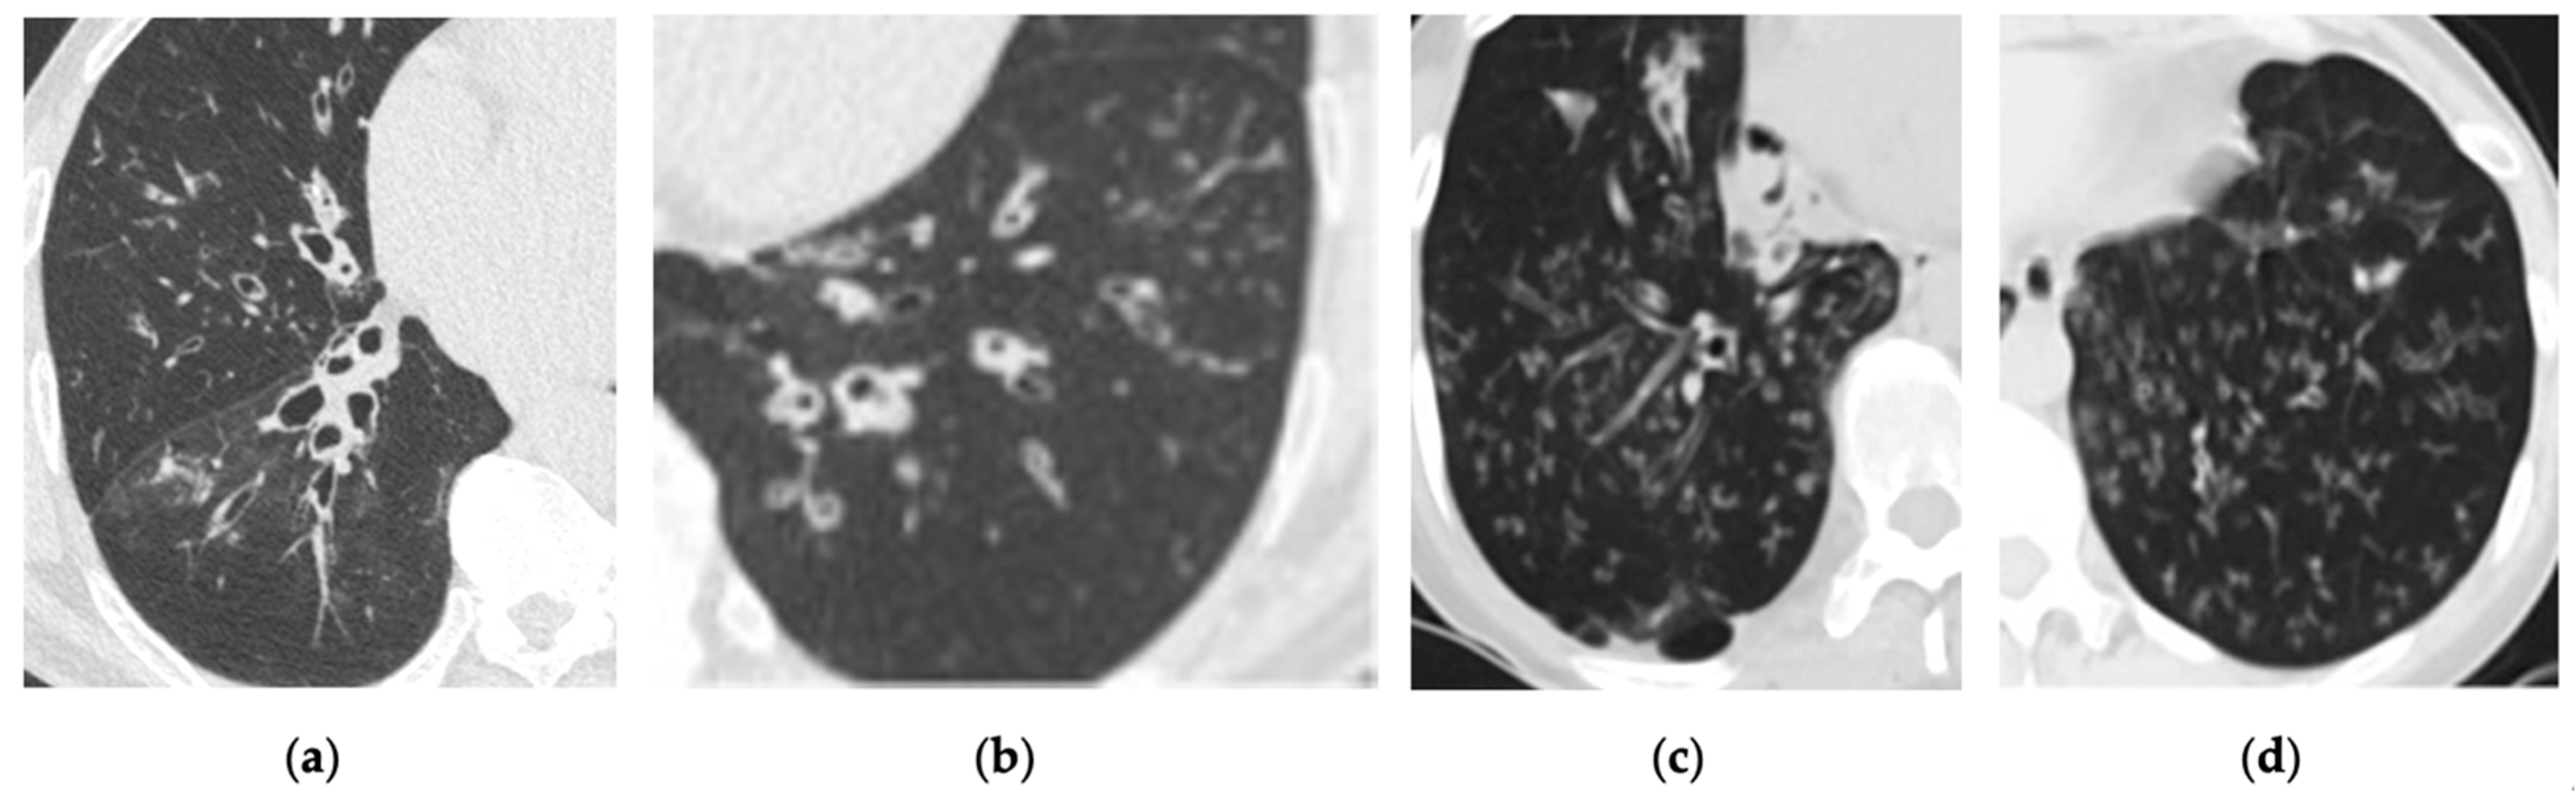

- Figure 4: The replacement figure provides a clearer and more focused depiction of bronchiectasis and infectious bronchiolitis.